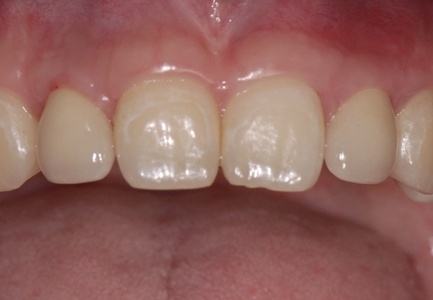

Abbildungen 1 und 2 zeigen einen typischen Defekt der konturgebenden Knochenprojektion im Frontzahnbereich, wie er z. B. – wie hier dargestellt – nach Trauma oder Entzündung entstehen kann (Abb.1 und 2).

Die Rekonstruktion sollte insbesondere in diesem sensiblen Bereich nicht simultan mit der Implantation, sondern präimplantologisch erfolgen. Die Rekonstruktion der sagittalen Projektion im Frontzahn- sowie der transversalen Projektion im Seitenzahnbereich der Juga alveolaria stellt einen hohen Anspruch an die chirurgische Behandlung dar, zumal die Wiederherstellung der gemeinsam mit der Hartgewebsunterlage geschrumpften Weichgewebsdecke bereits vor Behandlungsbeginn berücksichtigt werden muss. Bei Patienten mit hoher Lachlinie, eigentlich aber in jedem Fall der Rekonstruktion des Alveolarfortsatzes, muss die ursprüngliche Projektion nicht nur wiederhergestellt, sondern sogar leicht überdimensioniert gestaltet werden, da das Implantat – gegenüber einer natürlichen Zahn wurzel – von 1 mm – 1,5 mm Knochen allseitig umgeben sein sollte.